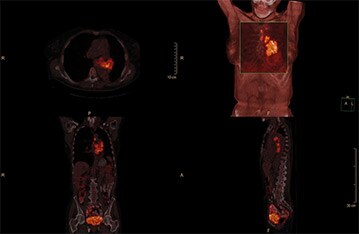

×Sharp моделирует и корректирует эффекты от функции распределения точки томографа, компенсируя тем самым недостатки разрешения на реконструированных изображениях и уменьшая их размытость. Коррекция артефактов частично объемного эффекта на ПЭТ-изображениях осуществляется благодаря использованию эффективного итерационного алгоритма Люси-Ричардсона, основанного на методе максимального правдоподобия. Изображения больного с раком легкого, реконструированные с помощью xFine, демонстрируют повышенную выявляемость поражений.

Технологии ×Sharp дает возможность получать изображения, на которых поражения и границы органов отображаются с высоким контрастным разрешением.

Изображения предоставлены клинической больницей Зальцбургского университета, Австрия